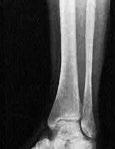

Fracture de fatigue et vasculite d’effort (exercice-induced vasculitis) chez une joggeuse impénitente.

Prof. Em. J-M Lachapelle